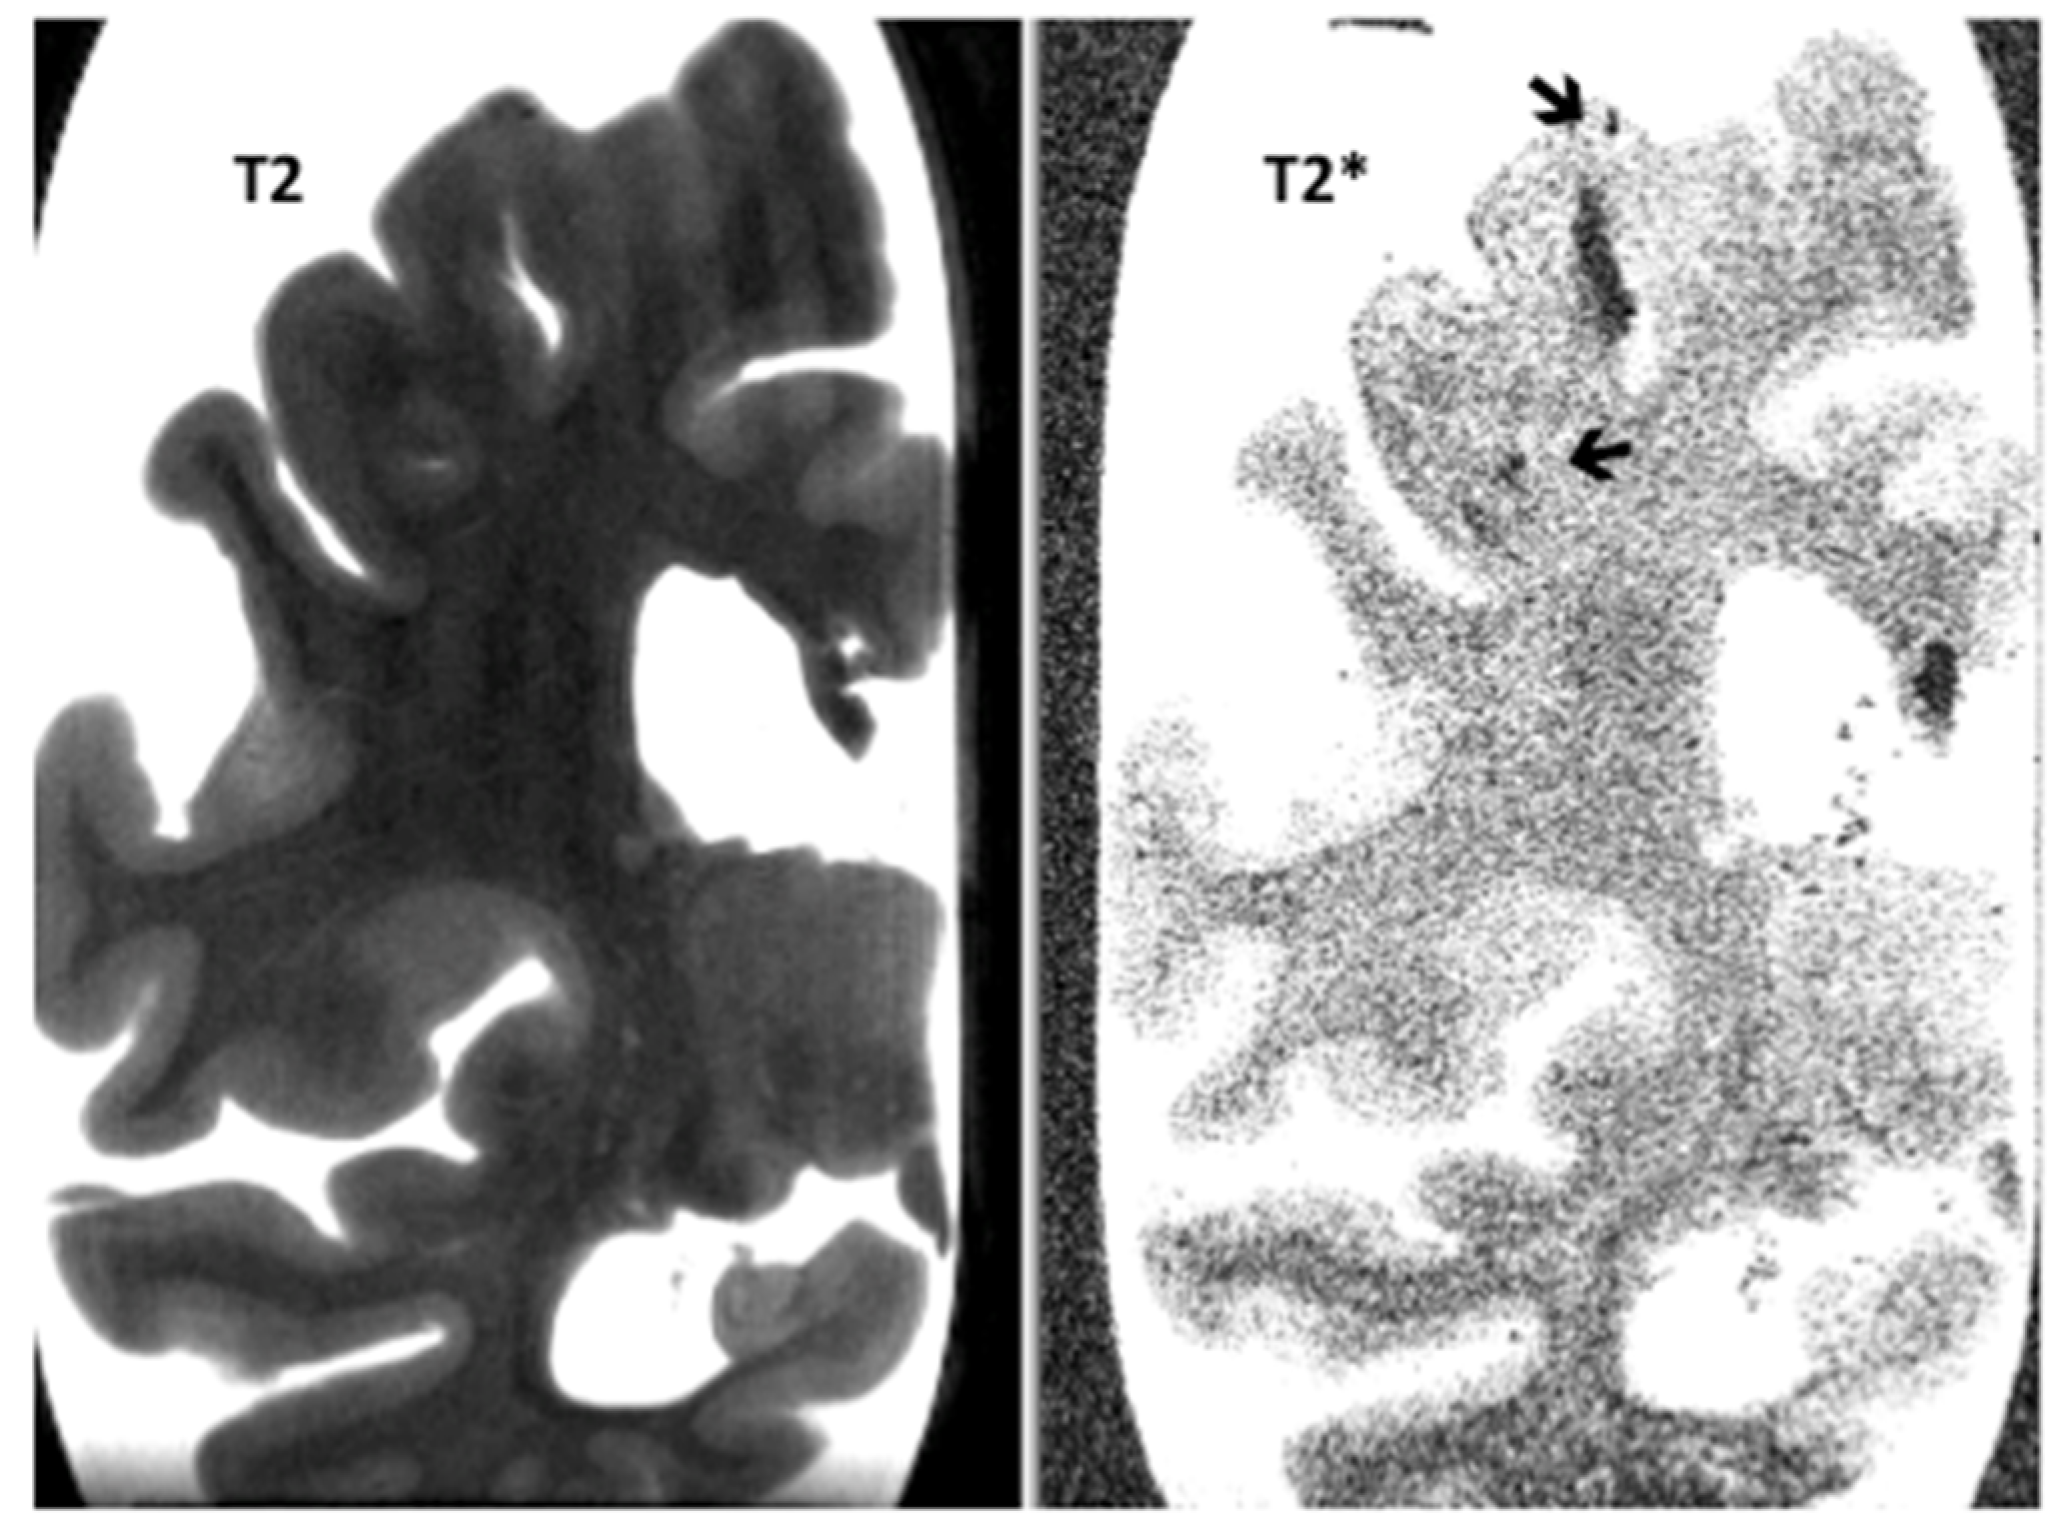

Post-Mortem 7.0-Tesla Magnetic Resonance Imaging of the Hippocampus in Progressive Supranuclear Palsy with and without Cerebral Amyloid Angiopathy

3. Results

| Hippocampal micro-bleeds | 0.9 (0.6) | 0.4 (0.5) | NS |

| Neocortical micro-infarcts | 0.4 (0.7) | 0.4 (0.6) | NS |